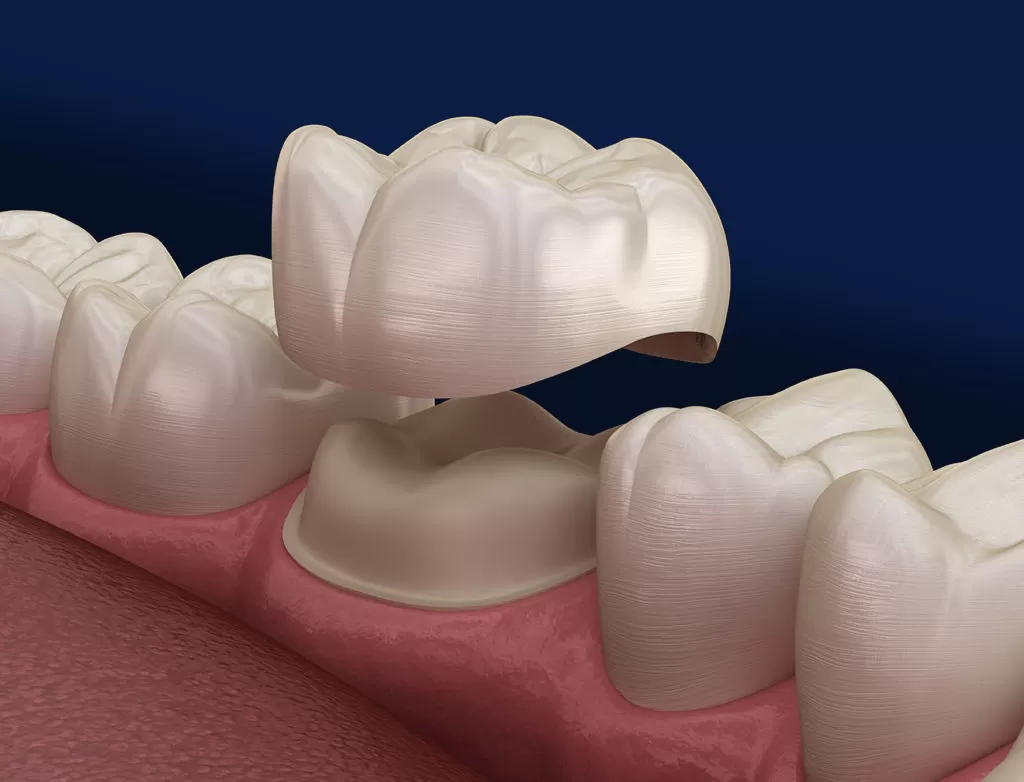

Crowns:

Dental crowns are tooth-shaped caps that are placed over a damaged or decayed tooth. They are used to restore the tooth's shape, size, strength, and appearance. Crowns can be made from various materials, including porcelain, ceramic, metal, or a combination of these materials. The choice of material depends on factors such as the location of the tooth, the extent of damage, and aesthetic considerations.